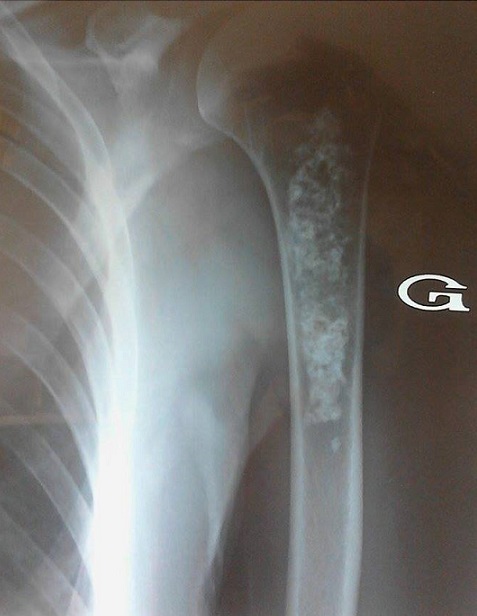

Les complications ostéo-articulaires du diabète de type 2 sont diverses parmi lesquelles certaines sont fréquentes comme la capsulite rétractile et la cheiro arthropathie diabétique. D'autres sont méconnues et difficilement rattachées au diabète. Nous rapportons l'observation d'une femme de 56 ans aux antécédents de diabète de type 2 insulino nécessitant depuis 6 ans mal équilibré (HbA1C à 10%) et qui se plaignait depuis 2 ans de douleurs de l'épaule et du bras gauches d'intensité moyenne à modérée. L'interrogatoire ne révélait pas de fièvre ou de signes d'altération de l'état général. A l'examen, il existait une douleur à la palpation du tiers supérieur du bras gauche sans arthrite de l'épaule ni limitation à la mobilisation active et passive de celle-ci. A la biologie, le bilan phosphocalcique, les phosphatases alcalines, le bilan rénal et la numération formule sanguine étaient sans anomalies. Il n'y avait pas de syndrome inflammatoire biologique. La radiographie de l'épaule était normale. A la radiographie du bras, il existait une image diaphysaire ostéocondensante irrégulière et en motte du tiers proximal de l'humérus sans effraction de la corticale. Cet aspect était typique d'un infarctus osseux ancien bien que la localisation à l'humérus ne soit pas fréquente. L'infarctus osseux peut être favorisé chez l'adulte par un traitement corticoïde ou la consommation d'alcool. Plus rarement, il peut être révélateur d'une maladie de gaucher de l'adulte mais il reste idiopathique dans environ 50% des cas.